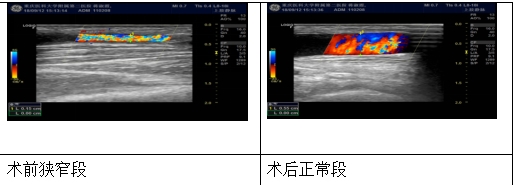

PTA球囊扩张术就是在超声引导下,通过皮肤表面穿刺血管,送入球囊扩张导管对血管的狭窄部位进行扩张,或者对血管的狭窄部分进行扩张,或者对血栓形成部分进行血栓压迫,使狭窄部分矫正达到或大于正常血管内径,是目前治疗动静脉内瘘狭窄的最新技术。

可随时观察血流情况,及时发现可能的血栓形成。

定期复查:要加强对内瘘的评估和保护,如果透析过程中出现血流量不足,静脉压升高等情况,则应及时检查,如狭窄大于50%,要及时进行治疗。